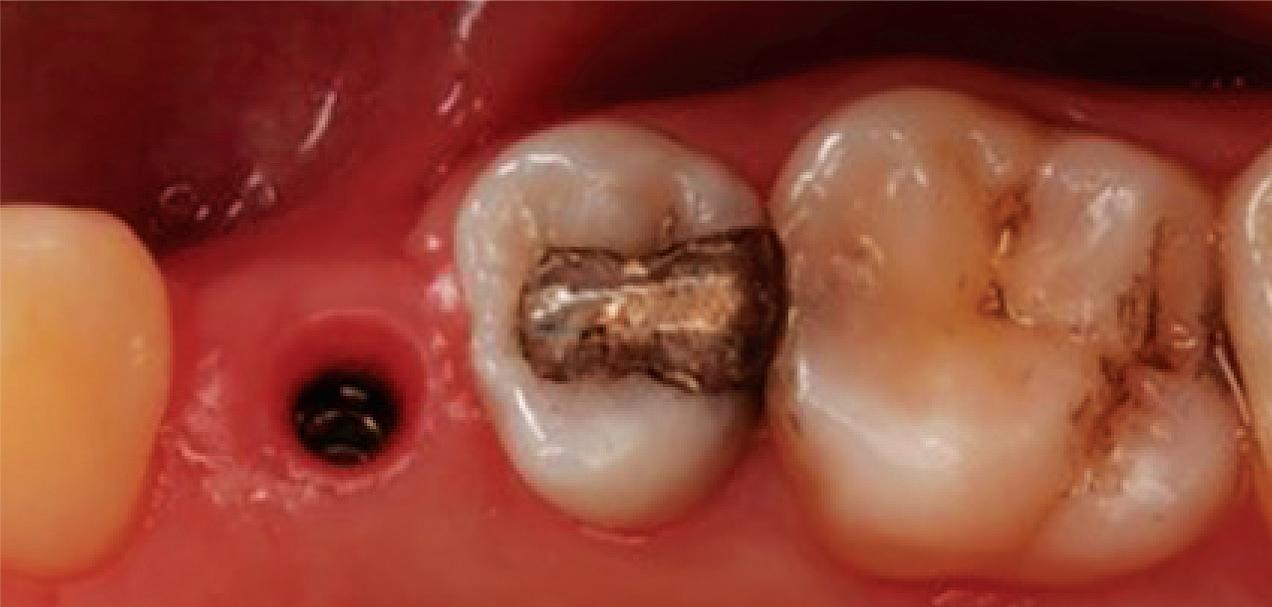

Clear radiographs are essential to accurate diagnosis and are a special test that dentists per form regularly many times throughout the day. Following the ALARA principle, we want to ensure we take a minimal number of radio graphs to ensure low radiation dosage so to repeat radiographs due to operator error should be avoided. The use of film holders allow the clinician to visualise how the radiographs should be taken to optimise the clarity of the image and ensure the diagnostic value of the image. Hawe Solutions x-ray film holders...

Figure 1: Radiographic Image of implants do not demonstrate bone loss due to the bisecting angle of the radiograph taken.

Figure 2: Radiographic image in a paralleling technique of implants dem onstrate moderate peri-implantitis with bone loss that will necessitate treatment.

• Allow exact posi tioning of the film or phosphor plate relative to the tooth - no bending and thus no distortion;

• Require no guesswork - exclusive, automatic reliance on the extraoral aiming and centring device;

• Deliver semi-reproducible images (quasi standardisation)the use of film holders allows some sense of reproducibility for assessment over time; and

• Produce optimally clear radiographs.